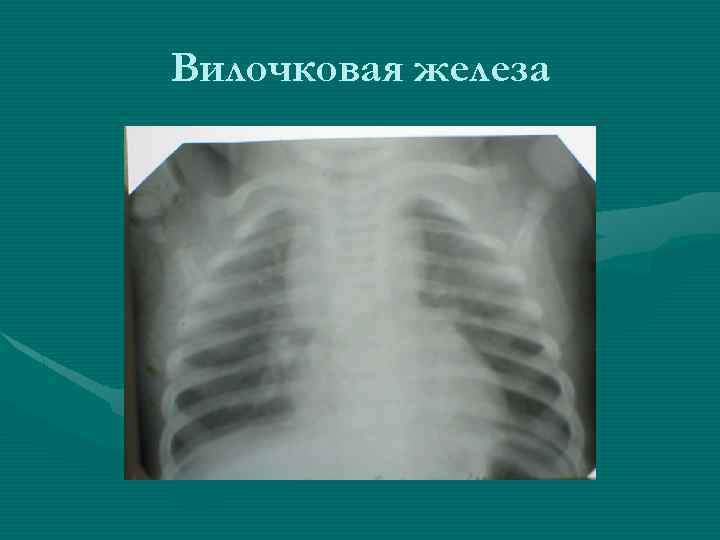

Тимомегалия: что это такое и как проявляется